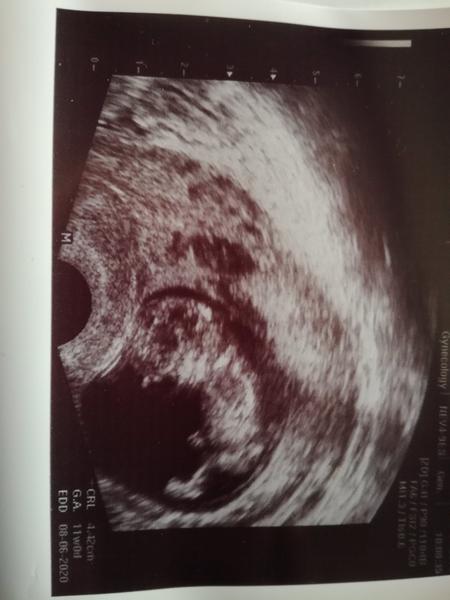

Takze devcata asi zde nemam co už pohledavat. Puvodne jsem mela podle MS mit TP 27.6. dnes kdyz jsem si byla potvrdit tehotenstvi tak na nas vykouklo prekvapko, ono to je vetsi nez 8+2, velikostne odpovida 11+0 a TP kolem 8.6.2020

Takze je mozne mit i menstruaci a byt tehotna 😂 ma to ruce nohy, hybalo se to jako ryba na suchu. Všem preji at to dopadne 💛